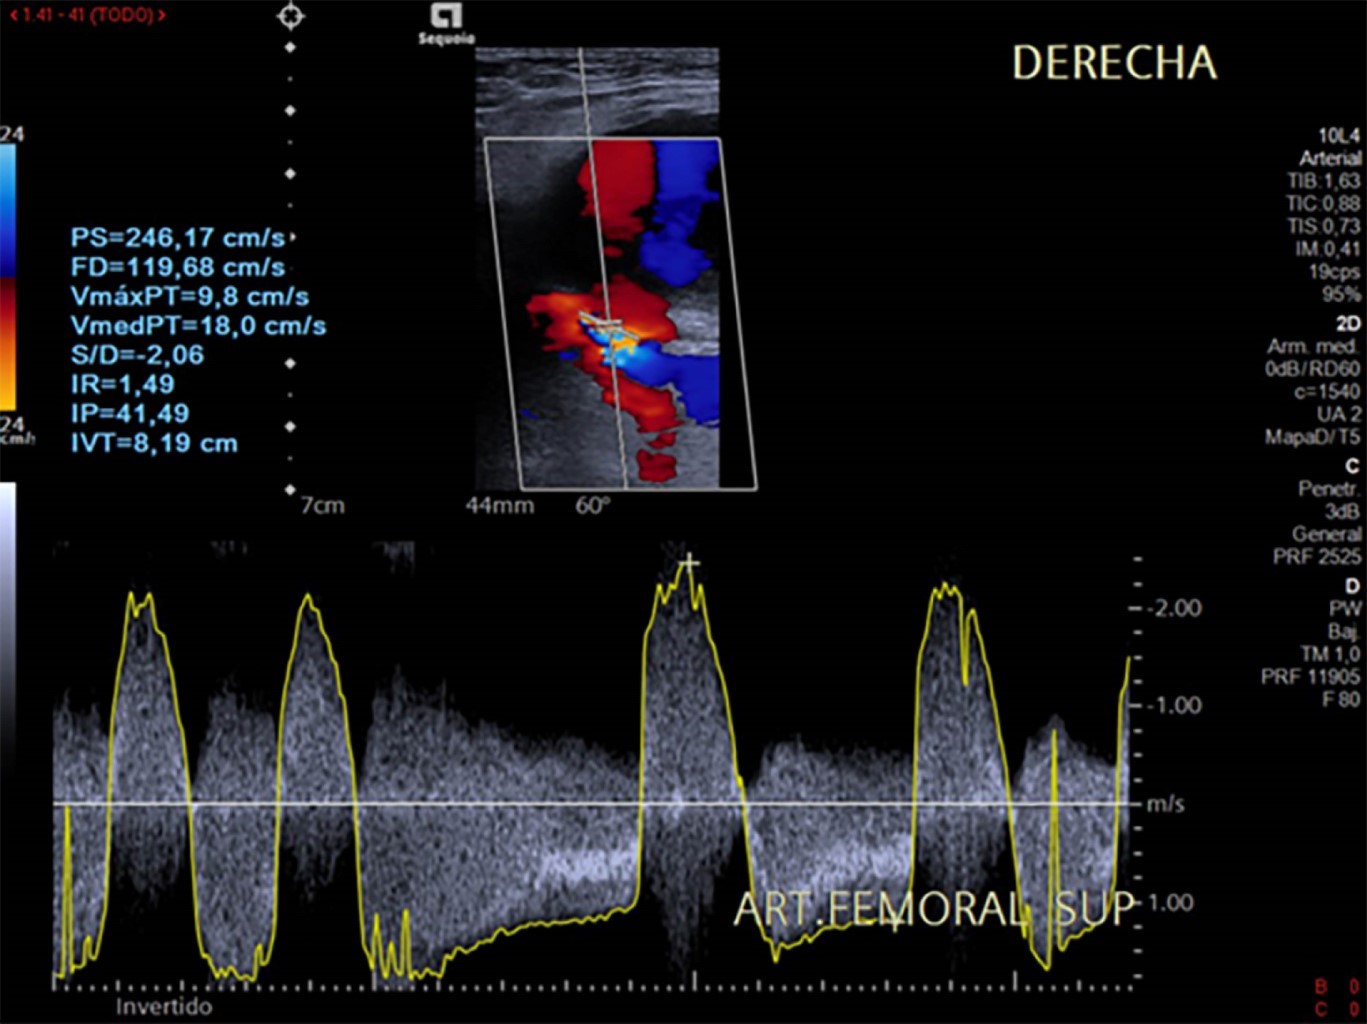

El pseudoaneurisma femoral es una saculación de las capas arteriales de la arteria femoral, siendo una de las principales causas la punción en las intervenciones de cateterismo vascular. El ultrasonido Doppler es el estudio de elección para su diagnóstico. Su incidencia es del 2-8% cuando se realizan angioplastia/stent coronarios. Masculino de 76 años con pseudoaneurisma en extremidad inferior derecha donde el ultrasonido muestra un pseudoaneurisma con hallazgos clásicos con fenómeno en "Ying-Yang" y de aliasing en sitio de comunicación e índice de resistencia elevado.

Hombre de 76 años con fibrilación auricular, a quien se le realiza coronariografía diagnóstica con abordaje femoral derecho. Después de ese evento en el postoperatorio se identifica evolución de lesión focal adyacente al sitio de punción, la cual era dolorosa e incrementaba su volumen e induración de forma diaria, por lo que se solicita ultrasonido Doppler de miembro inferior derecho para su valoración encontrándose pseudoaneurisma de la arteria femoral derecha (Figuras 1 y 2).

El diagnóstico de un pseudoaneurisma se debe realizar con ultrasonido Doppler, dentro del cual las características a buscar son la imagen en "Ying Yang", velocidad picosistólica e índice de resistencia altos, tamaño, dependencia arterial específica y tamaño del cuello aneurismático. Se puede realizar tomografía o resonancia magnética complementaria en caso de requerirse para acompañar su valoración en términos de extensión en casos complejos.2